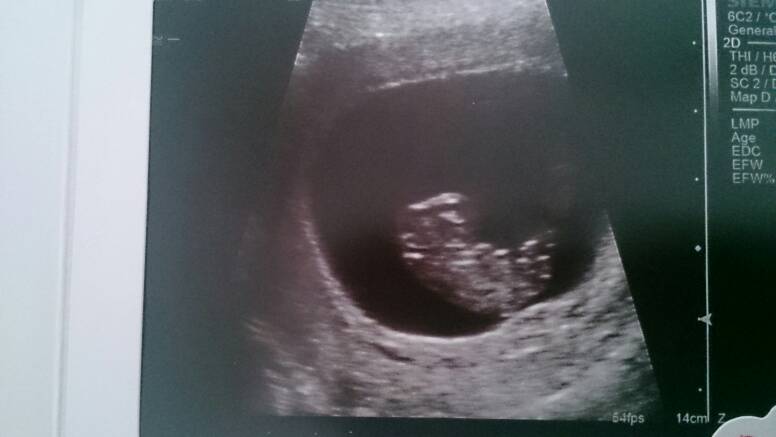

Sorki bo zdjęcie se zdjęcia..

Przez brzuch wszystkie, pierwsze 8t3 drugie dwa 8t6d.

Lilith o kurcze super widac dzidzie! Dzieki za zdjecia, to moze ja teraz tez bede sie upierac przy usg brzusznym? Sama nie wiem....W sumie to mam troche metlik w glowie, czesc osob mowi ze usg zadne nie ma wplywu na malucha, czesc mowi ze kazde usg ma wplyw a to dowcipne to juz w ogole inwazyjne grzebanie i lepiej tego nie robic.... Wkurza mnie to,mze kazdy mowi co innego, a ze jestem po stracie to jestem podatna na te wszystkie dobre rady:/:(

Lilith A zdjęcia bomba! Pierwszy raz takie widzę i nie mogę się napatrzec :D